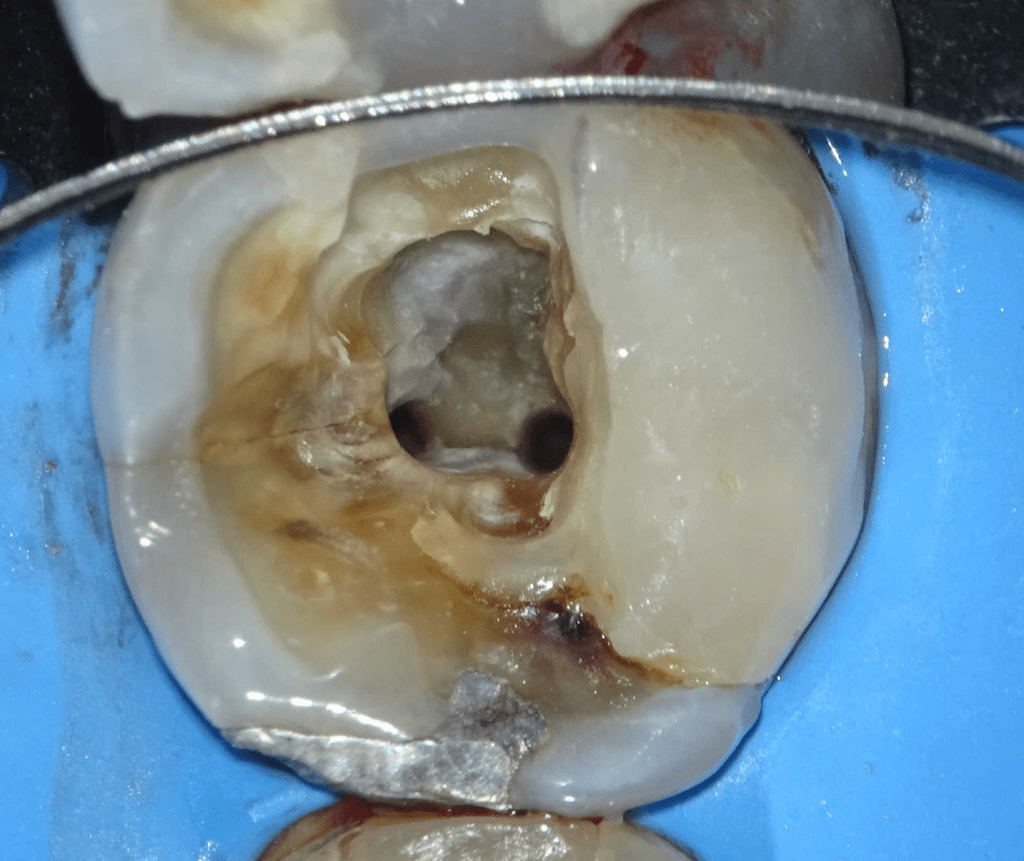

Pulpotomía biodentine + reco preendio